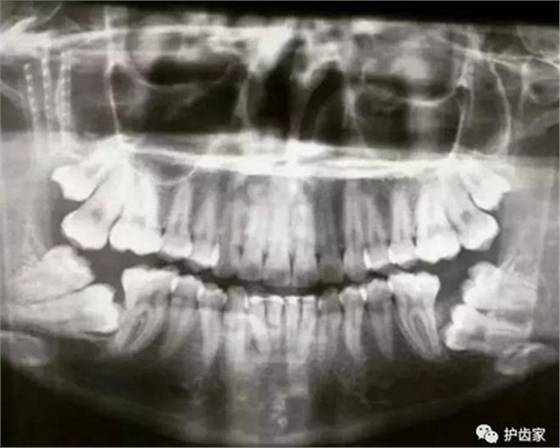

拍片的必要性

拍片是為了了解智齒周圍情況,也是為了了解智齒結構,牙根結構千變?nèi)f化,有可能是融合成一個根,也可能是八爪根。不同牙根不同位置及方向,只有通過拍片來確認。

拍片也為了了解下頜神經(jīng)與智齒的關系,一般離得近,有醫(yī)療風險的,基本沒有醫(yī)生愿意拔,現(xiàn)在沒人為了幾百元,賠上自己的職業(yè)生涯。誰都怕拔智齒,敲打智齒,一不小心,碰到神經(jīng),就攤上大事了。有理都說不清。

通過拍片可以了解牙齒本身:生長方向,牙根數(shù)目,牙根是否彎曲,膨大等。

與重要解剖結構的位置關系:如上頜磨牙與上頜竇的關系;下頜磨牙與下頜神經(jīng)管的關系;兒童在混合牙列期恒牙與乳牙胚的關系等??梢詼p少拔牙的風險。

預知其他病變:如頜骨內(nèi)有無埋伏牙,多生牙,囊腫等。

拔智齒必須拍片,一方面是看智齒的位置及方向,為拔智齒制定拔牙方案。另一方面,了解智齒周圍情況,了解下頜神經(jīng)位置,規(guī)避醫(yī)療風險。當個醫(yī)生還得前怕狼后怕虎的,大家多體諒牙醫(yī)!